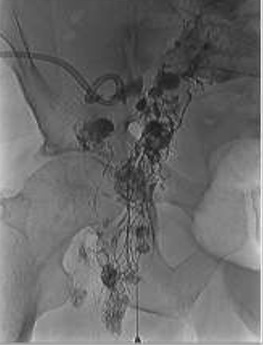

左前斜位显示有淋巴漏 位于先前经皮引流的治疗盆腔囊肿的旁边。通过导管被注射酒精硬化治疗。 后续超声随访显示,的淋巴囊肿消失。 |